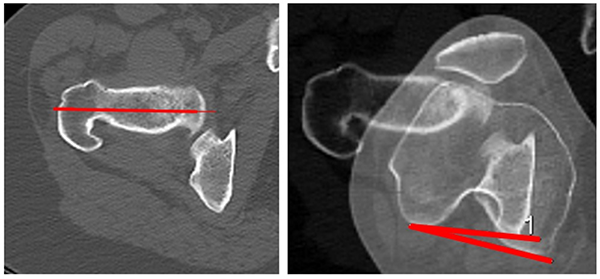

Anteversión femoral (AF)

Esta medición se realiza en extensión completa. En este caso seleccionamos y superponemos dos imágenes axiales según el método descripto por Hernández:16 una donde se observa cabeza, cuello femoral y trocánter mayor, con otra donde se visualiza el corte de la línea bicondílea. El ángulo se forma por la intersección de una línea que pasa por el centro de la cabeza y centro de cuello femoral y la línea bicondílea, de esta manera se obtiene la anteversión femoral. Se expresa en valores positivos cuando es anteversión y negativos cuando es retroversión. Valor normal: 11°,9 (fig. 13).

Figura 13: Anteversión femoral. Se mide con la superposición de dos cortes axiales: uno donde se visualiza cabeza y cuello femoral, y otro, el cóndilo femoral. El ángulo de traza por la intersección de la línea que pasa por el centro de la cabeza femoral y el centro del cuello femoral, con la línea bicondílea. Normal: 11° (8°-15°).

Torsión tibial externa (TTE)

Esta medición también se realiza en extensión completa. Se seleccionan y superponen dos imágenes: una axial del platillo tibial, lo más proximal posible donde se visualice cortical posterior, y la otra a nivel de la sindesmosis tibioperonea distal. Se traza una línea paralela a la cortical posterior de la tibia, y otra pasando por el centro de ambos maléolos. El ángulo de torsión tibial externa resulta de la intersección de ambas. Yoshioka describe como valor normal 23° en hombres y 27° en mujeres,17 según Dejour: 33°,11 (fig. 14).

Figura 14: Torsión tibial externa. Se mide superponiendo dos cortes tomográficos, uno lo más proximal en tibia, y el otro a través del tobillo donde se visualicen ambos maléolos. El ángulo se forma por la intersección de la tangente posterior a cortical de tibia proximal y la línea que pasa por el centro de ambos maléolos en tobillo.

Torsión tibial externa - línea epicondílea

Esta medición se realiza en extensión completa. Es el ángulo formado por la intersección entre la línea epicondílea femoral y la línea bimaleolar. Este ángulo es equivalente a la suma de la torsión tibial externa más rotación femorotibial (fig. 15).

Figura 15: Torsión tibial externa línea epicondílea. Se superponen cortes de cóndilos femorales donde se ve arco romano y tobillo . El ángulo se forma por la intersección de la línea bicondílea y la línea bimaleolar. El valor suele ser la sumatoria de la torsión tibial externa más la rotación femorotibial.